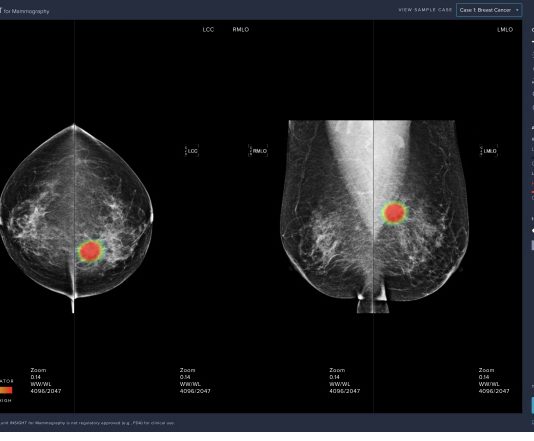

의료 인공지능(AI) 업체 루닛(대표이사 서범석)은 자체 개발한 유방암 진단 보조 소프트웨어가 식품의약품안전처 허가(의료기기 3등급)를 받았다고 31일 밝혔다. 해당 제품은 ‘루닛 인사이트 MMG’로 29일 식약처로부터 국내 판매 허가(인허가 제품명 Lunit INSIGHT for Mammography)를 받았다. 루닛 인사이트 MMG는 루닛과 연세대학교 세브란스병원, 서울아산병원, 삼성서울병원이 공동 개발한 제품이다.루닛 인사이트 MMG는 인공지능기술을 기반으로 설계된 유방촬영영상...